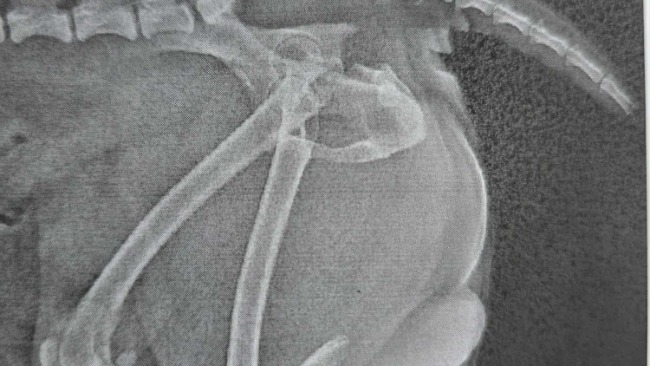

Tango (imię schroniskowe) przyjechał do nas z innej lecznicy do której trafił po wypadku. Odpowiednio zaopatrzony i zaopiekowany przyjechał z paskudną diagnozą - złamanie kości miednicy. Szybka burza mózgów, kontakt z lecznicami, kontakt z rehabilitantami i udało się znaleźć odpowiednie miejsca dzięki którym psiak w przyszłości będzie mógł wrócić do pełnej sprawności.

Tango wie, że nie zostawimy go bez pomocy, ale niestety ta pomoc jest kosztowna. Koszty samego zabiegu opiewają na blisko 2000 złotych. Do tego dochodzą jeszcze koszty opieki medycznej oraz rehabilitacji. Część z tych środków jesteśmy w stanie pokryć. Jednak nie wszystko. Dlatego zwracamy się do Was - zwierzolubów, ludzi, których los zwierząt nie jest obojętny. Organizujemy zbiórkę na operację Tango i wierzymy, że pieniądze nie staną na przeszkodzie pełnego powrotu do zdrowia tego urwisa. Ten młody psiaczek jeszcze niewiele w życiu widział a już musiał tyle wycierpieć Wspólnymi siłami możemy dać mu jeszcze wiele lat szczęścia Możemy na Was liczyć? Zamieszczamy zdjęcia Tango wraz ze zdjęciami RTG jako (jak to mawiają w policji) dowód w sprawie